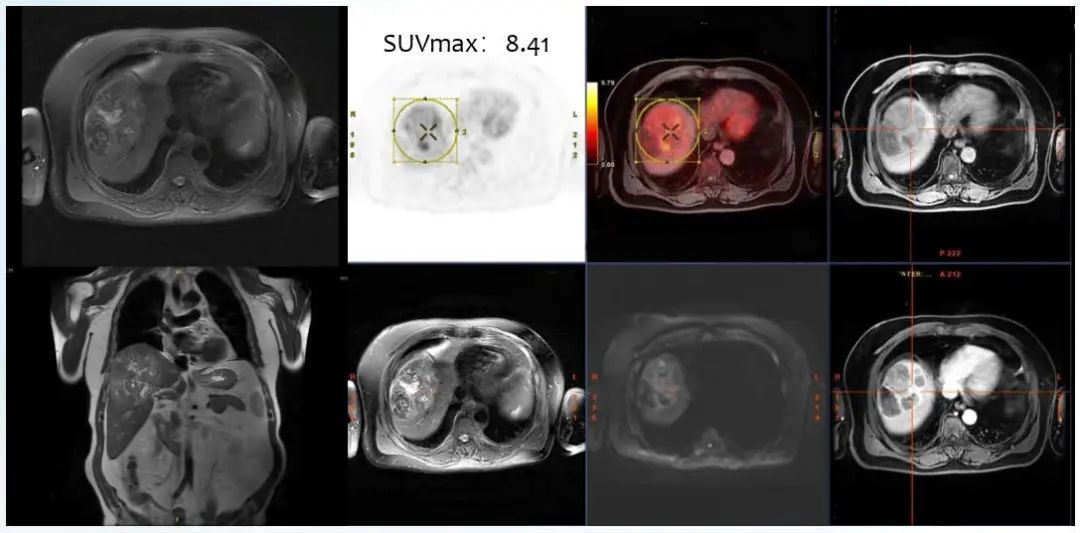

图1. PET-MRI 功能影像特征

- 影像学(PET-MRI)呈高摄取。